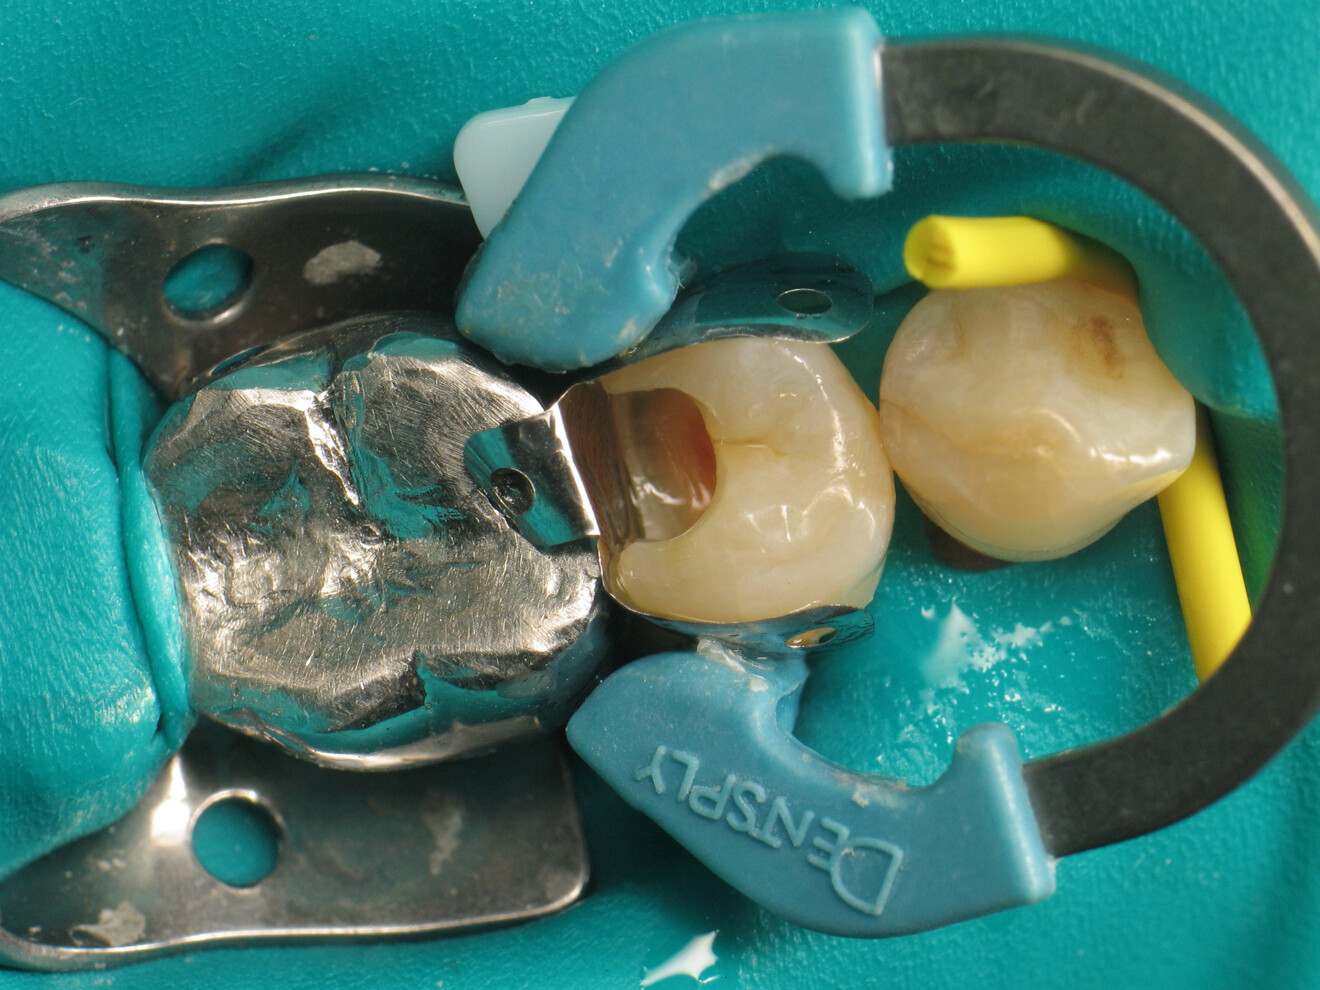

The clinical case described in this article concerns a Class II cavity in a premolar (tooth #45) restored using a thermo-viscous composite (Fig. 1). The tooth was isolated with a dental dam (Fig. 2). The cavity was then cleaned (Fig. 3). In order to obtain an anatomically correct distal wall, a matrix, a wedge and a ring were placed (Fig. 4). The tooth enamel was then etched for 30 seconds and the dentine for 15 seconds (DeTrey Conditioner 36, Dentsply Sirona; Fig. 5) and then rinsed and dried thoroughly (Fig. 6). Owing to the thinness of the remaining dentine, pulp protection (Telio Desensitizer, Ivoclar) was also applied (Fig. 7).

Fig. 4: Placement of the proximal matrix.